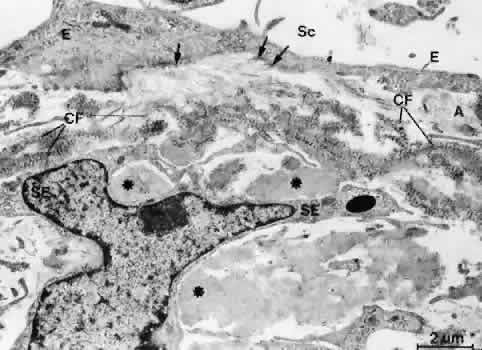

Serial tangential sections showed in the electron microscopic dimension that the fiber network belongs to a complicated system that connects the inner wall endothelium with the trabecular lamellae. The elastic-like fibers of the cribriform layer form a regularly arranged network of interlacing fibers that are continuous with the elastic-like fibers of the adjacent corneoscleral lamellae (Fig. 13). Toward the inner wall endothelium, bundles of fine fibrils separate from the elastic-like fiber sheaths and connect the subendothelial network of elastic-like fibers either with the endothelium of Schlemm's canal or with the subendothelial basement membrane material. Therefore, these fibrils were called “connecting fibrils” (Fig. 14).22 In the adult eye, the connecting fibrils are embedded in a homogeneous ground substance that is digestible with chondroitinases.14

Fig. 13. Electron micrograph of a tangential section through the inner wall of Schlemm's canal showing the subendothelial elastic-like fiber network (arrows) of the cribriform layer (× 10,000).

Fig. 14. Electron micrograph of an oblique sagittal section through the inner wall of Schlemm's canal. The connecting fibrils (CF) derive from the sheaths of elastic-like fibers and are attached to the cell membranes of the inner wall endothelium (E, arrows). Asterisks indicate plaque material. A, subendothelial fine fibrillar material; Sc, Schlemm's canal;SE, subendothelial cells. (Rohen JW, Futa R, Lütjen-Drecoll E: The fine structure of the cribriform meshwork in normal and glaucomatous eyes as seen in tangential sections. Invest Ophthalmol Vis Sci 21:574, 1981)

Electron microscopic investigations reveal thatthere are optically empty spaces between the connecting fibrils. In an experimental study on monkey eyes, we found that the area of such “empty spaces” in the cribriform region is positively correlated with outflow resistance values measured by anterior chamber perfusion.23 We therefore assumed that these spaces may represent preferential pathways for aqueous outflow through the cribriform layer. Calculations about the pressure gradient across the cribriform and subendothelial layers lead to the statement that if the spaces were really empty, the extracellular material and cells in this region might provide only insignificant resistance to aqueous outflow.24,25 If, however, the preferential pathways are coated with a 0.35-μm-thick glycosaminoglycan layer, the pressure gradient would rise to the physiologically observed values. It is possible that hyaluronan, glycosaminoglycan, or proteoglycan gel, lost during the embedding procedure, also contributes to formation of outflow resistance.26 This hypothesis was recently supported by experimental studies in the living monkey where in fact 80% to 90% of outflow resistance was shown to be located in front of Schlemm's canal, probably within the cribriform layer of the TM.6